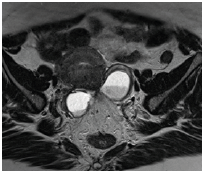

Progrès marquants de l’imagerie par IRM en gynécologie

Les améliorations technologiques de l’IRM permettent des diagnostics très fiables notamment dans l’endométriose, les myomes utérins, la caractérisation des masses annexielles et le bilan d’extension des cancers utérins.